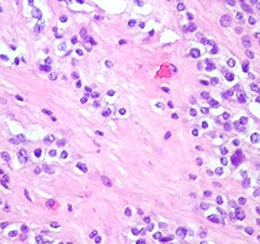

Micro: pleomorphic round discohesive sheets. lots o mits and necrosis

- prominent angiocentric and angiodestructive growth, esp at periphery, where they appear to accumulated in perivascular space and are angiodestructive

IHC: (+) CD20 (diffuse), CD3 / 5 (stain scattered T cells), EBER-ISH in tumor nuclei, very high Ki67